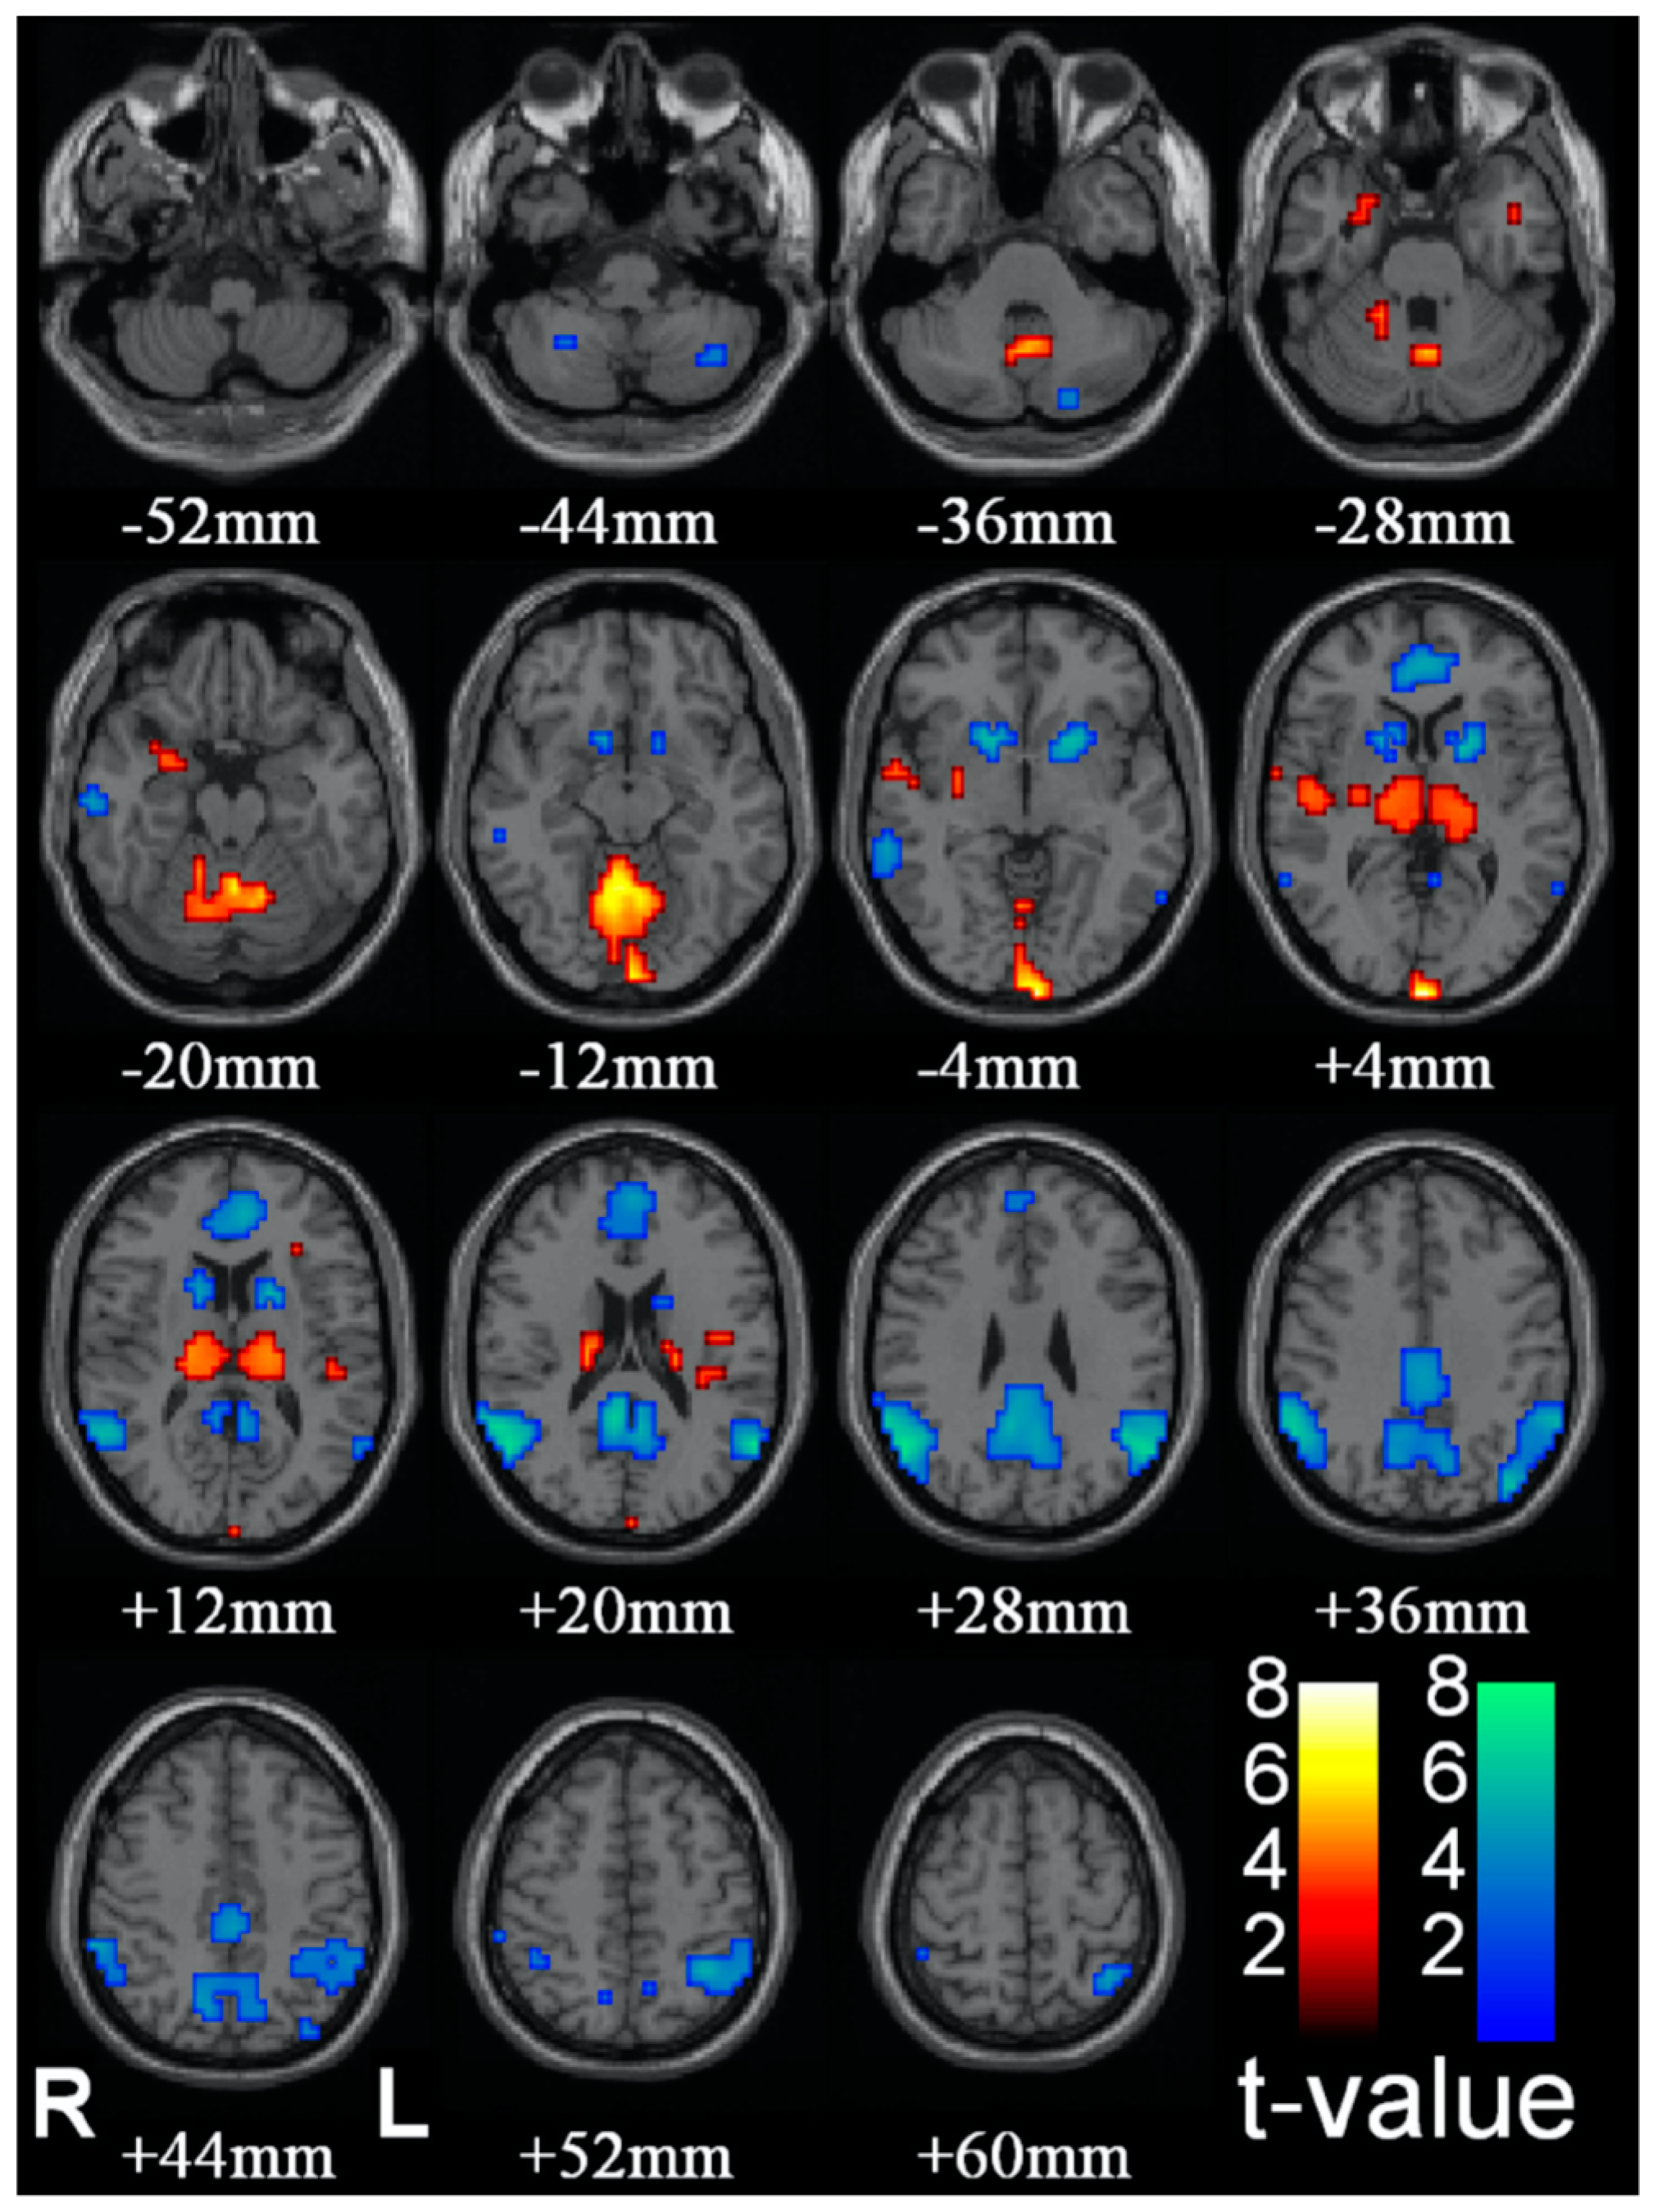

8. Evaluation of Concrete Proposals for the Substrate of Consciousness

Blumenfeld [40], see [41], develops a proposal for the substrate of C* based on clinical indices of observable disruptions in the state of C*, such as epileptic absence (petit-mal) seizures. Group data of the effect of such seizures are reproduced in Figure 4. The logic of the analysis is that absence seizures represent a reportable and behaviorally corroborated loss or steep reduction of C*, though they are not accompanied by the loss of muscle tone associated with sleep. The subject will remain in an upright seated posture, for example, but stop speaking for the few seconds which comprise the duration of the seizure, and exhibit confusion on returning to C*. Thus, brain regions showing a decrease in activation during this period should be associated with the normal C* that is disrupted during this period, while those showing increases may best be interpreted as being inhibitory centers.

The brain regions showing consistent reductions in fMRI activation during petit mal absences are the ventral striatum in the region of the nucleus accumbens and the caudate nucleus (blue patches from −4 to +12 mm in Figure 4) and medial and lateral components of the DMN (blue patches from +4 to +60 mm in Figure 4). Remarkably, some brain regions show marked increases in fMRI activation during the absences, notably the thalamus (orange patches from +4 to +12 mm in Figure 4) and what appear to be some medial structures in the cerebellum (orange patches from −20 to −12 mm in Figure 4). These are probably best interpreted as inhibitory brain loci, with the thalamic inhibition emanating from the reticular nucleus of the thalamus, which is an inhibitory net surrounding the thalamus that acts as a gating mechanism to control sensory input to and from the cortex.

Components of both the dorsal and ventral striatum have been associated specifically with the conscious/non-conscious boundary in perceptual tasks [42,43]. However, these forms of differential activation may not relate directly to C* per se, since the manipulation determines when a particular stimulus reaches the level of C*, which is then processed for the Yes response, as opposed to the No response when it is not seen. These responses require both differential motor programming and a sense of reward when seen, which are the well-established functions of the dorsal and ventral striata, respectively. However, neither involves any change on the overall conscious state of the participants, but only its contents. This kind of paradigm therefore does not address the core issue of C* per se.

Figure 4. Changes in brain activity during epileptic absence seizures (from [40]).